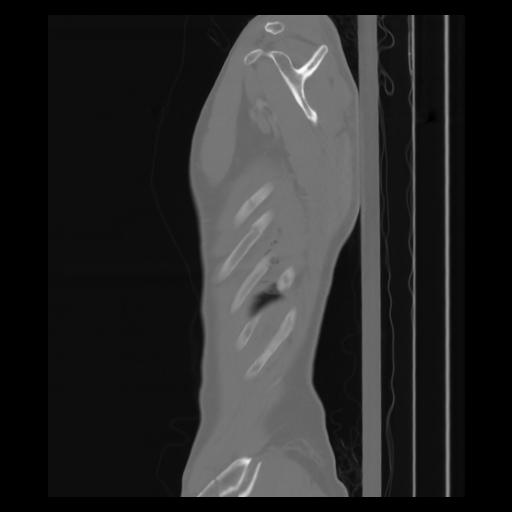

30 CUERPO,CE,Sagittal,3.000,CUERPO,Sagittal,